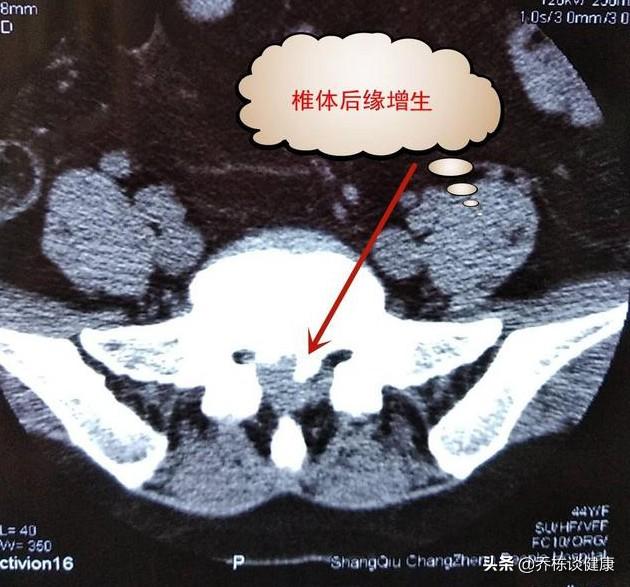

石灰化と過形成のフィルムを撮る。

回復して何年も経ってから、腰椎椎間板ヘルニアが石灰化したとか、後縦靭帯が石灰化したとか、椎間腔が狭くなったとか、骨棘ができたとか、脊椎が不安定になったとか、そういうことが判明するケースもあるが、いつものことだが、何事も対症療法であり、症状がなければ変性は許容範囲であり、変性の急速な進行を遅らせるだけである。